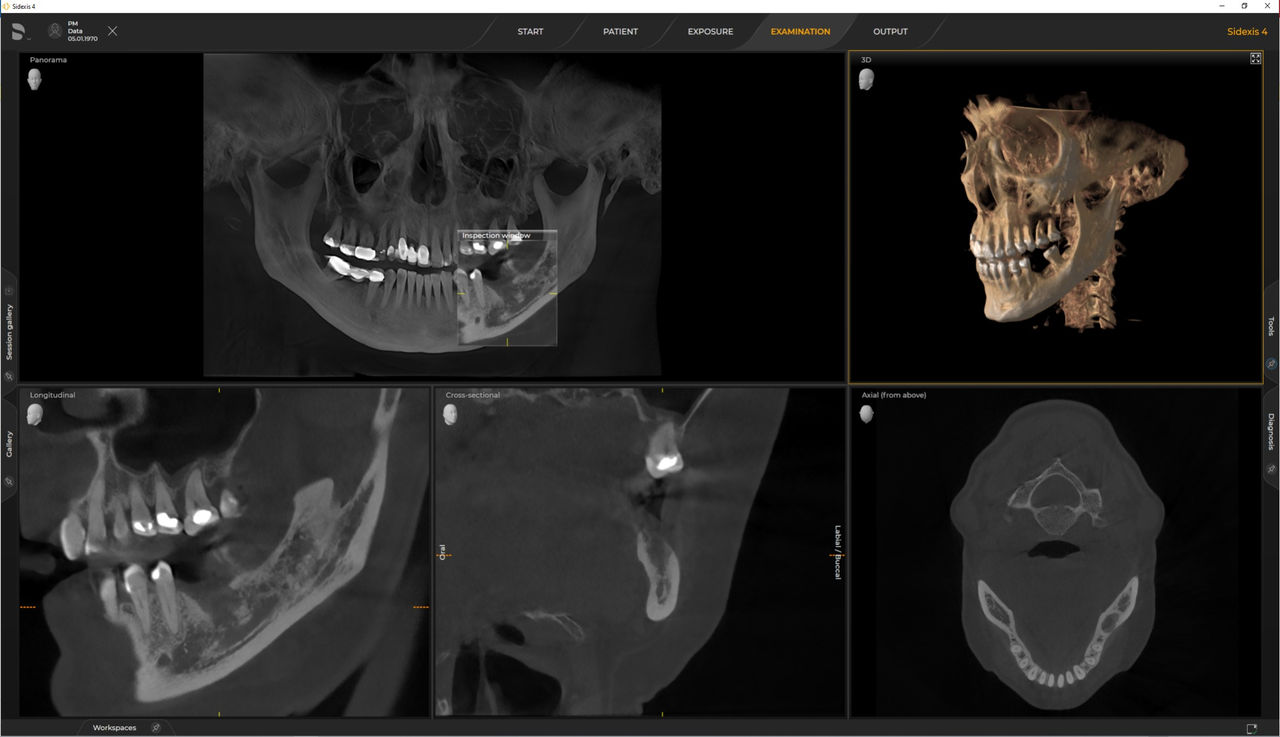

Os requisitos seguem os requisitos dos softwares de processamento de imagem Sidexis 4 e Axeos. Para obter mais detalhes, consulte Requisitos do sistema Sidexis 4 e requisitos de instalação do Axeos.

As unidades 3D da Dentsply Sirona funcionam exclusivamente com Sidexis 4. No entanto, a migração de dados do Sidexis XG para o Sidexis 4 é muito fácil. O Sidexis 4 permite uma experiência digital completa com as ferramentas mais recentes.